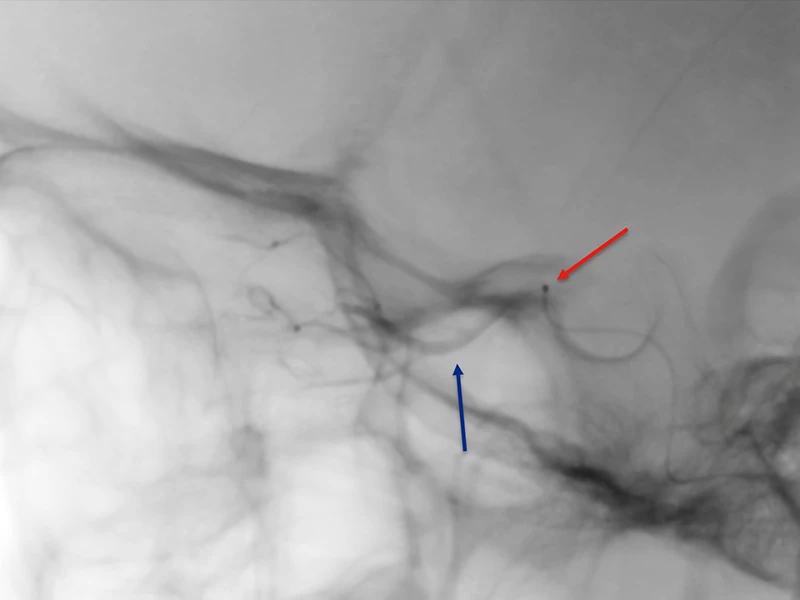

Dr. Fifi delivered the first of three rounds of the chemotherapeutic agent melphalan, spaced a month apart, directly to the tumor site, working with a Mount Sinai neurointerventional team that included a pediatric anesthesiologist. This required gaining access through the femoral artery and snaking a microcatheter into the carotid and then the ophthalmic artery using X-ray guidance.

X-ray showing delivery of intra-arterial chemotherapy agent. The red arrow is showing the microcatheter tip in place and blue arrow is pointing to dye in the ophthalmic artery.